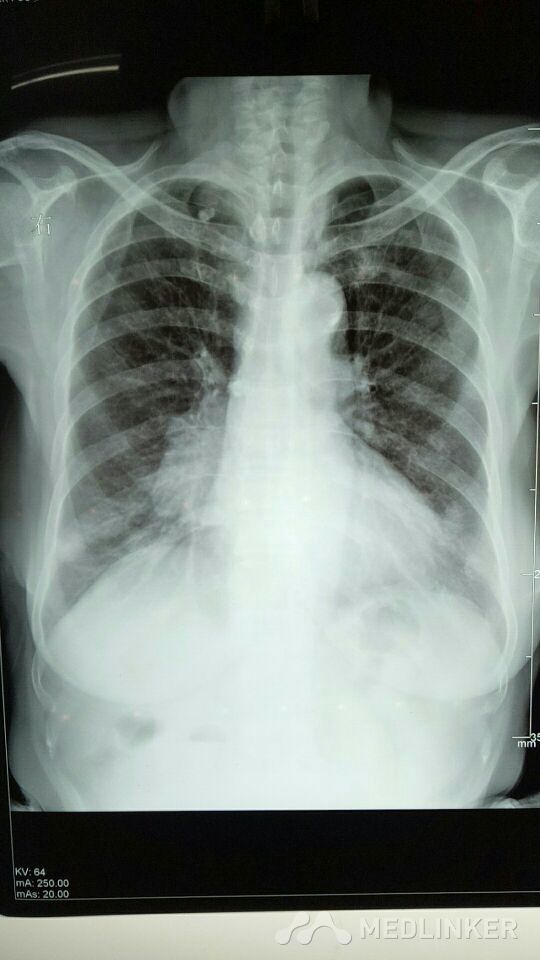

右侧肺门增大

放射科检查